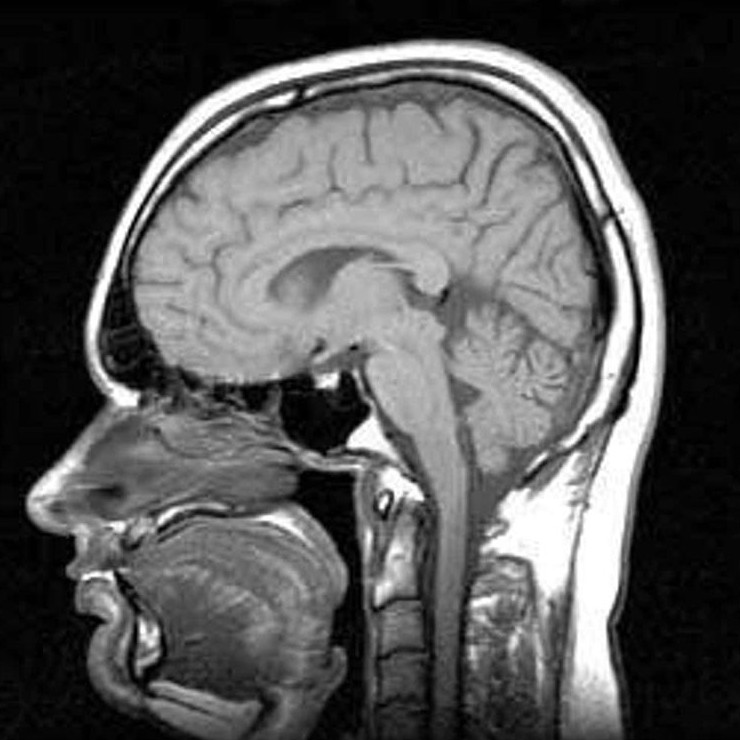

Электросудорожная терапия, или ЭСТ, когда-то была известна как «электрошоковая терапия». Суть процедуры проста: через мозг пациента пропускают электрический ток, вызывая контролируемый судорожный приступ. Сегодня этот метод иногда применяют для лечения тяжёлой депрессии и некоторых других психических расстройств. Современная процедура проводится под наркозом и с соблюдением строгих медицинских стандартов. Однако история ЭСТ куда более тревожная. В первые десятилетия её применения эксперименты проводились довольно грубо, а иногда и откровенно жестоко. Вот несколько фактов из прошлого этой терапии, которые сегодня звучат довольно мрачно.